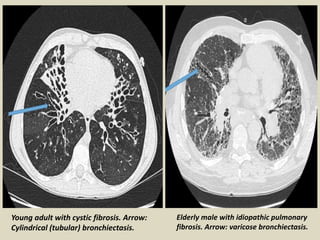

Young adult with cystic fibrosis. Arrow:

Cylindrical (tubular) bronchiectasis.

Elderly male with idiopathic pulmonary

fibrosis. Arrow: varicose bronchiectasis.